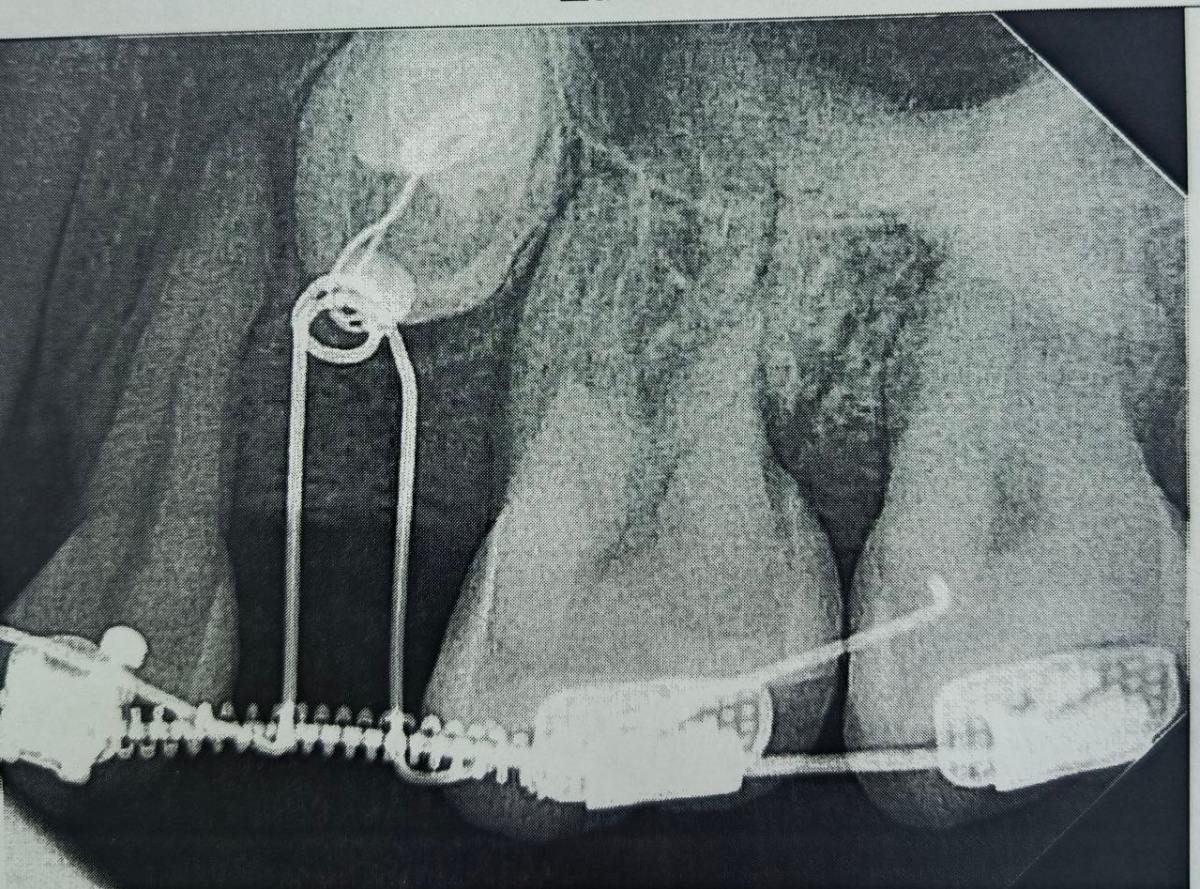

Диагностика с помощью компьютерной томографии показала сложную картину – в челюсти находились два непрорезавшихся зуба.

При этом, в самом зубном ряду был дефект – один зуб полностью отсутствовал, а другой был сильно меньше нормы.

Врачи приняли решение «вытянуть» непрорезавшиеся зубы и поставить их в ряд, в правильное положение.

Сначала пациентке установили брекет-систему, полтора года с ее помощью в зубном ряду создавалось место.

Когда пространство было подготовлено, хирурги провели операцию: раскрыли десну, чтобы обнажить коронки непрорезавшихся зубов, и зафиксировали на них специальные ортодонтические кнопки.

С помощью миниатюрных пружин и рычагов, подключенных к брекет-системе, зубы начали медленное движение.

На сегодняшний день один зуб уже полностью вышел из костной ткани и занял свое законное место. Второй успешно проходит последний барьер - кортикальную пластинку челюсти - и вскоре тоже встанет в ряд.